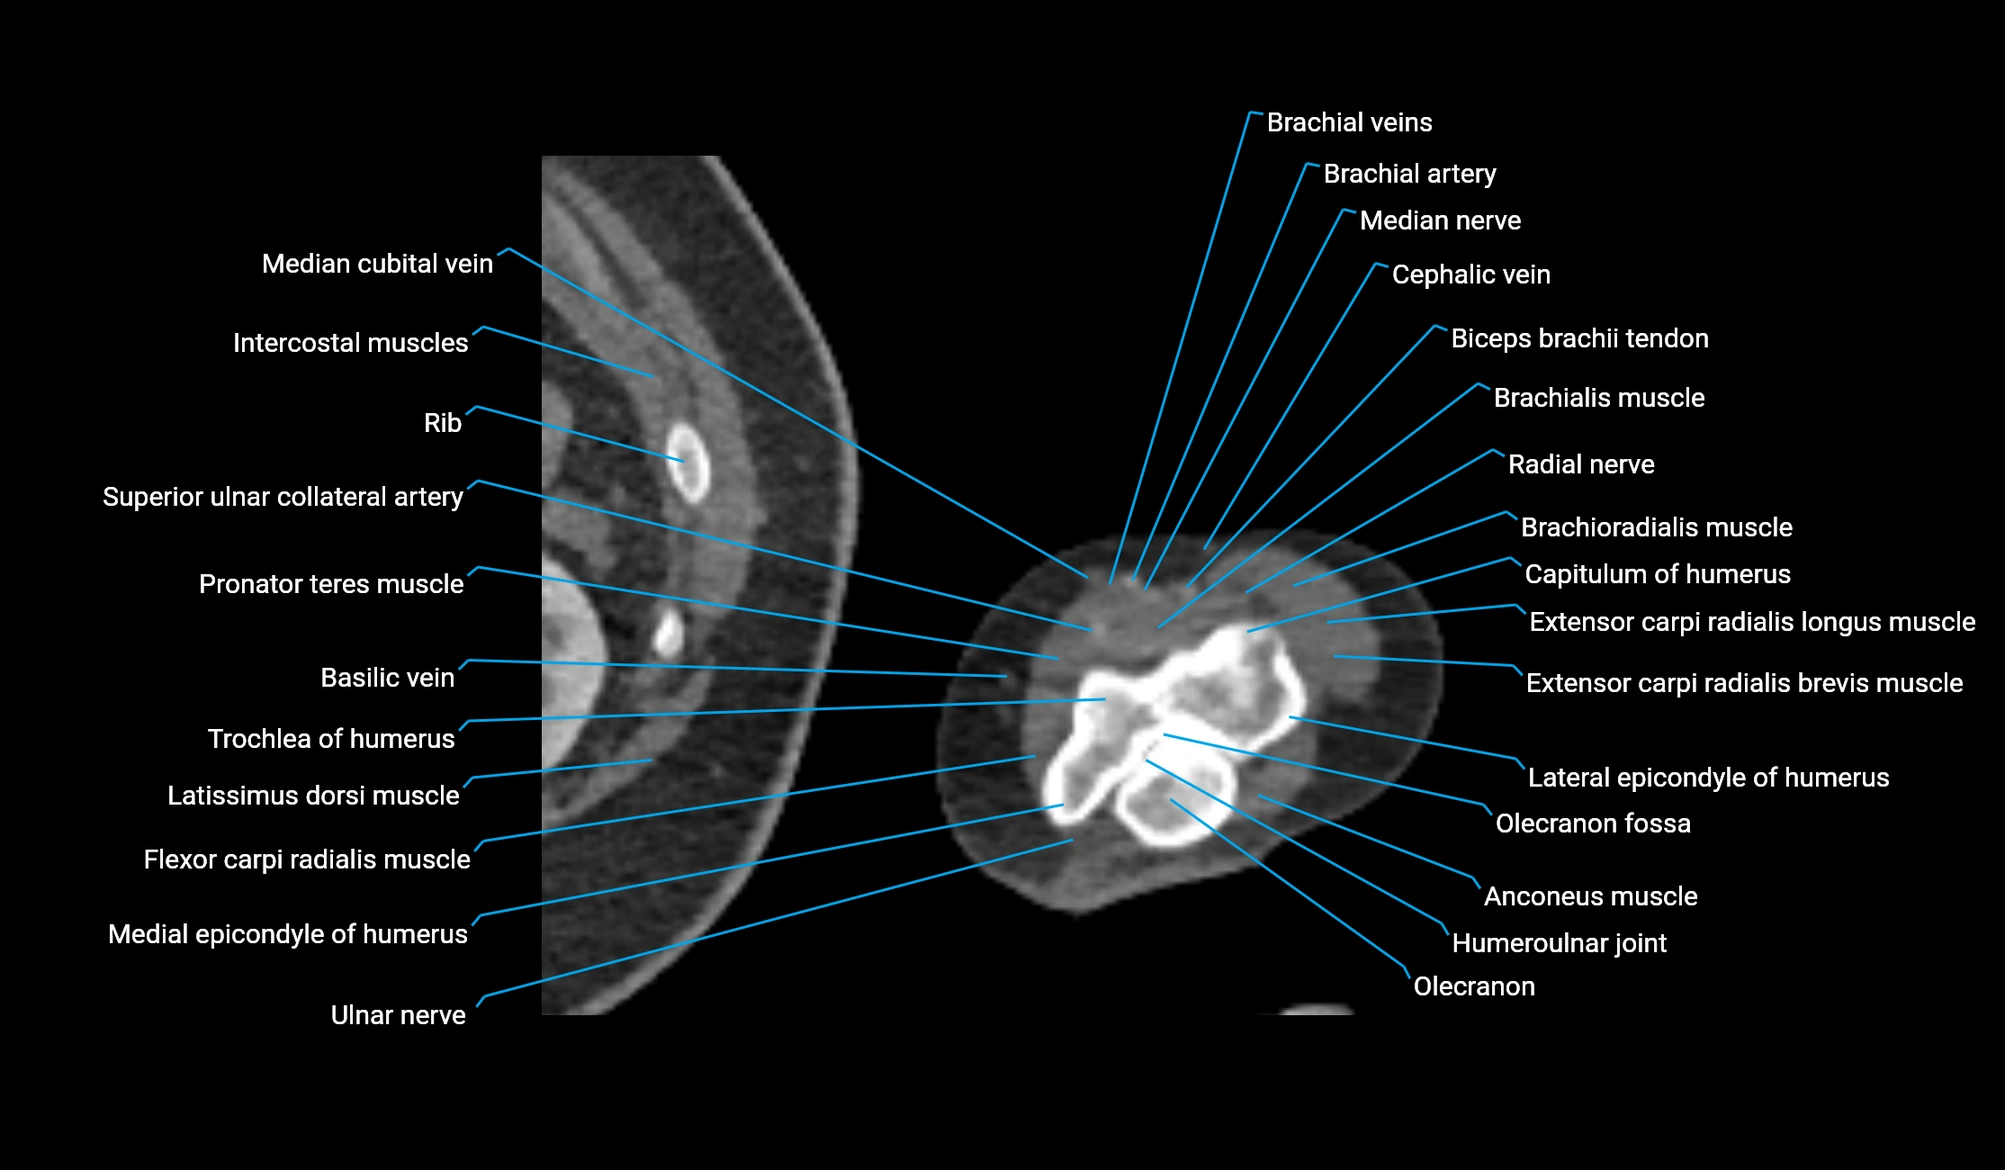

- Anconeus muscle

- Brachioradialis muscle

- Capitulum of humerus

- Extensor carpi radialis brevis muscle

- Extensor carpi radialis longus muscle

- Flexor carpi radialis muscle

- Humeroulnar joint

- Lateral epicondyle of humerus

- Medial epicondyle of humerus

- Median cubital vein

- Median nerve

- Olecranon

- Olecranon fossa

- Pronator teres muscle

- Superior ulnar collateral artery

- Trochlea of humerus